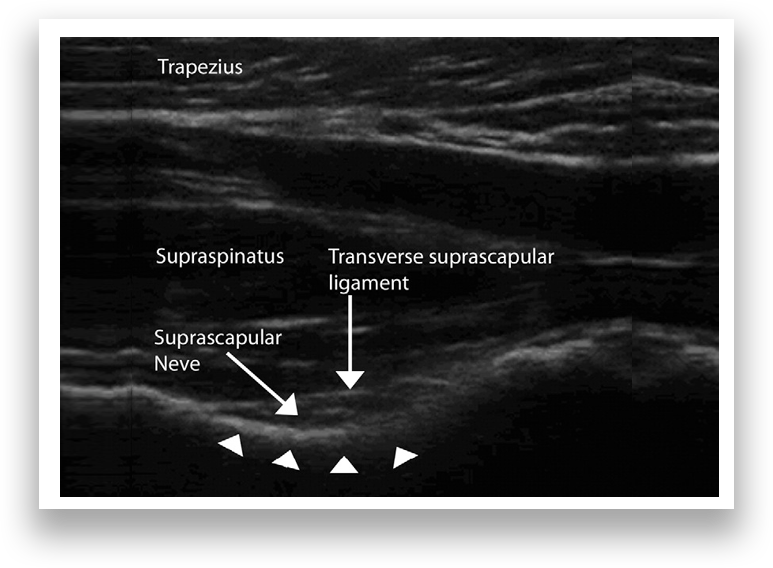

Shoulder anatomy, including bones (scapula, clavicle, humerus), muscles (rotator cuff), and ligaments.

X-ray/MRI scan overlay